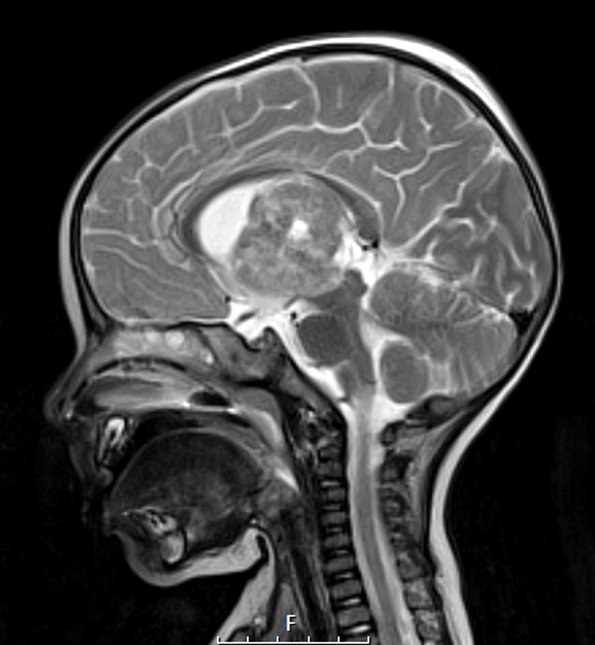

20A3 ATRT (NP24-888) T2W sag 2 - Copy

The tumor has a variegated appearance on T2-weighting with contrast administration.